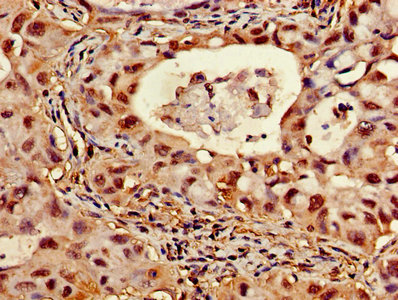

Immunohistochemistry of paraffin-embedded human lung cancer using CSB-PA002355HA01HU at dilution of 1:100